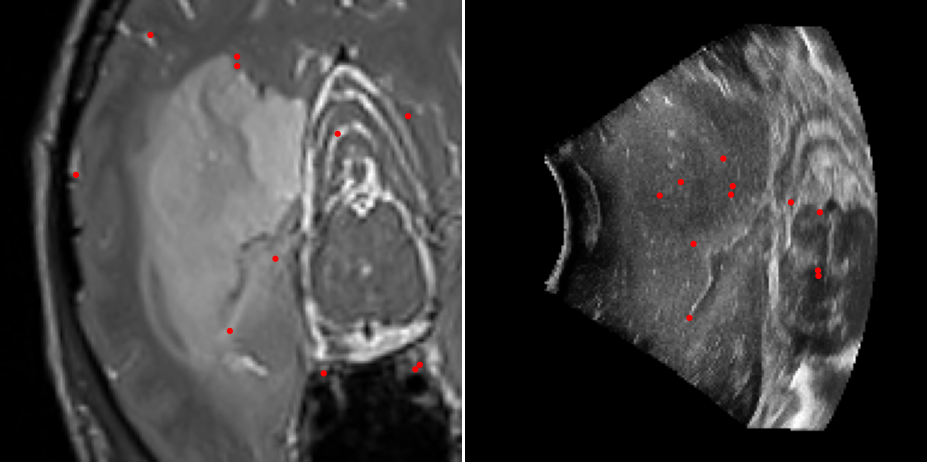

Refer to caption

Figure 5: MR slice #40 retrieved in US volume using descriptor matching.

We also perform a slice retrieval test to measure the discriminating properties of our method. We search for a target slice over the whole volume by matching n=200𝑛200n=200 keypoints from the target MR slice with m×d𝑚𝑑m\times d keypoints of the whole US volume. Results reported in Figure 5 show that our descriptor can successfully retrieve the target slice and discriminate it over other slices with an average 1.341.341.34 mm error within 20 slices and 2.482.482.48 mm error within 40 slices.